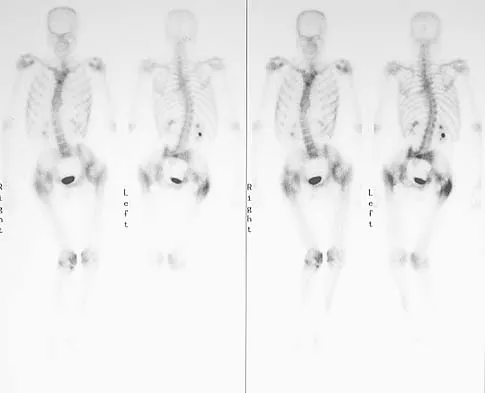

Figure 11a shows the AP pelvis radiograph of a 25-year-old man who sustained a spinal cord injury 10 years ago. A bone scan and a CT scan are shown in Figures 11b and 11c. To prevent recurrence after resection, management should consist of

Detailed Explanation

The studies reveal significant heterotopic ossification that appears to be mature. Following resection, the most reliable way to prevent recurrence is with low-dose external-beam radiation therapy. Bisphosphonate therapy can be considered; however, when terminated, heterotopic bone may reform. Heterotopic ossification is unrelated to the patient's endocrine status and is not associated with any metabolic abnormalities. Moore K, Goss K, Anglen J: Indomethacin versus radiation therapy for prophylaxis against heterotopic ossification in acetabular fracture. J Bone Joint Surg Br 1998;80:259.